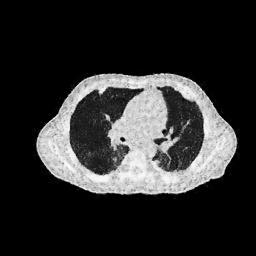

IV-C Few-View CT Reconstruction

In this section, the reconstruction performance of our proposed framework under few-view conditions will be tested. For the parallel and fan beam geometry, the number of views increases from to , uniformly distributing from to and to respectively. Such settings provide a complete benchmark of reconstruction performance, ranging from extremely sparse to relatively complete, full-view CT reconstruction. The experiment results are shown in Fig.5. Additionally, the ground truth, few-view ( views), and full-view ( views) CT reconstruction results of different methods are shown in the first and third rows of Fig.7 (parallel-beam, LIDC-IDRI dataset), and Fig.8 (fan-beam, LIDC-IDRI dataset).

To test the proposed framework’s performance on limited-angle reconstruction, we redo the experiment in the above section with the angular range changing from to for parallel-beam geometry and to for fan-beam geometry, one projection per degree. The experiment results are shown in Fig.6. Also, the ground truth and the limited-angle CT reconstruction results of different methods are shown in the row of Fig.7 (parallel-beam, LIDC-IDRI dataset), and Fig.8 (fan-beam, LIDC-IDRI dataset).

SNR/SSIM

16.31dB/0.55

20.83dB/0.83

13.37dB/0.61

16.65dB/0.79

13.40dB/0.73

16.85dB/0.65

22.47dB/0.78

14.25dB/0.63

22.99dB/0.62

19.51dB/0.56

(a) Ground Truth

30.15dB/0.85

(b) ASD-POCS

39.35dB/0.94

(c) RBP-DIP

27.10dB/0.78

(d) DIP

23.88dB/0.65

(e) MED50

20.59dB/0.60

(f) RED-CNN